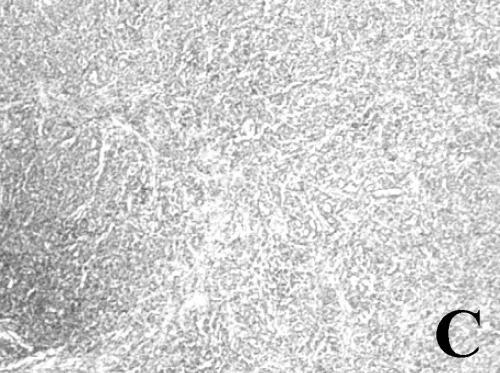

Figure 2. A case from the

SCI group. A. Appearance of the right lymph node. B. Necropsied

lymph node specimen cut sagitally. C. Histopathologic view of the lymph node (H&E, 100x). |

Follow-up,

Local Recurrence and Findings in the Necropsy

In the follow-up, neither the SCI nor the STI group showed local recurrence at the site of implantation. Thirteen SCI hamsters (86.7%) developed right axillary lymph node metastasis (Table 1), which was palpable between 4 and 12 weeks after the resection. This lymph node in the early stage was movable. After approximately 2 weeks, it became adhered to deep tissue and grew to 6 cm in diameter. When the lymph node reached this size, the animals died. In the necropsy, there was no local recurrence, or macroscopic internal-organ metastases. The metastatic axillary lymph node showed central necrosis (Figure 2). All lymph nodes were confirmed as metastasis at the histopathological and molecular level. The lungs, liver and pancreas did not show any metastases. The remaining two animals of this group without axillary lymph node metastasis did not have any metastases in their internal organs. The cause of death was unknown.